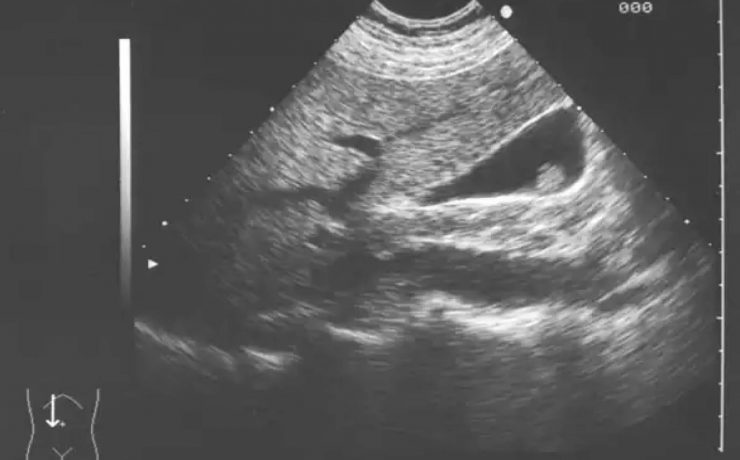

Patologías benignas de la próstata: prostatitis e hiperplasia prostática benigna.

Se realiza revisión detallada de la anatomía prostática y los principales factores que influyen en el aumento de volumen de la glándula prostática de origen patológico con diversas etiologías. Presentando como principales patologías la prostatitis y la hiperplasia prostática benigna. El término prostatitis incluye un conjunto de síntomas o disturbios